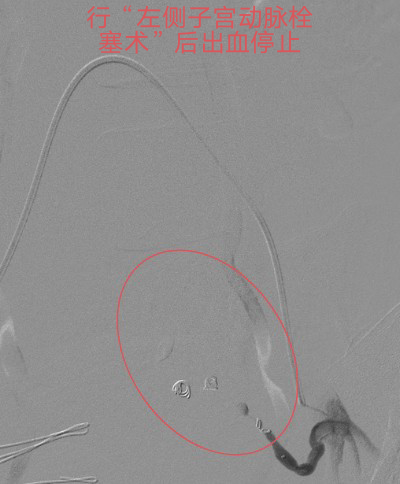

本着“生命至上”的原则,吴主任立即启动介入导管室为产妇施行“造影术”检查,造影发现产妇子宫动脉远端均有活动性出血,尤以左侧子宫动脉出血明显,血液不断外渗,病情紧急,止血治疗迫在眉睫!要知道产后大出血是非常凶险的疾病,不能有效止血可能需要切除子宫保命的!但患者才不到三十岁呀,正值青春年华,切除子宫对患者以后可是有非常大的影响。此时,能及时止血救命,又能保住子宫的微创介入止血法的优势就出来了!在患者及其家属的期盼和高度信任下,吴主任顺利为患者施行微创介入止血手术,术后患者子宫动脉出血停止,阴道出血减少,术后无需继续输血血压、血红蛋白均能维持稳定。术后经常规产后康复护理治疗后,患者病情稳定,没有异常阴道出血,现已康复出院。

行微创介入止血手术后出血停止